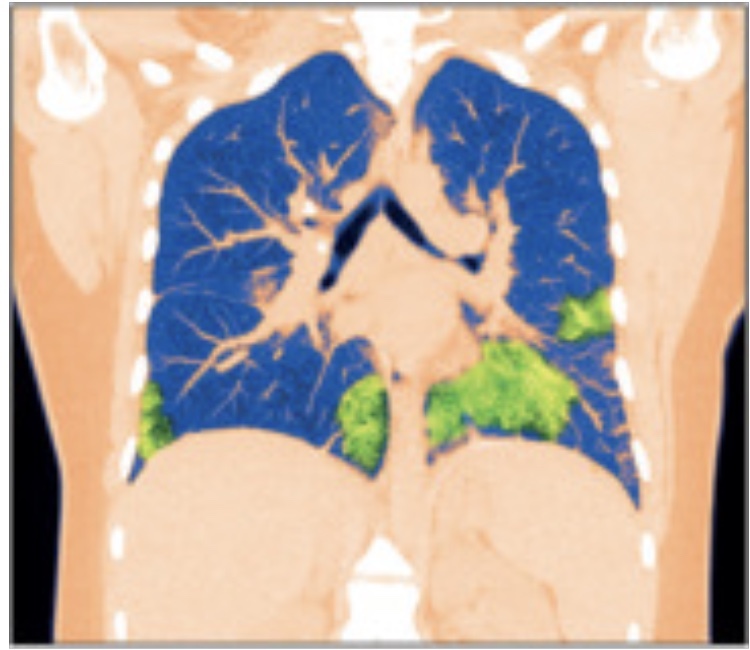

2019 年,在电子烟使用者中发现了电子烟或电子烟产品使用相关肺损伤 ( EVALI ),截至 2020 年 2 月 18 日,美国报告了近 3000 例病例,其中 68 人死亡。许多病例被认为与含有四氢大麻酚 (THC) 的产品和维生素 E 醋酸盐有关。最近,Hariri 及其同事在NEJM Evidence中报道了一系列四名患者患有与电子烟使用相关的慢性肺病。患者有 3 年至 8 年的使用史,并报告有胸痛和呼吸困难。使用包括高分辨率胸部 CT 在内的成像技术,作者观察到以气道为中心的小纤维化,包括缩窄性细支气管炎,并推测,鉴于症状出现的时间,这种模式很可能是由于电子烟的使用。有趣的是,在停止使用电子烟的患者中,疾病发生了部分逆转。